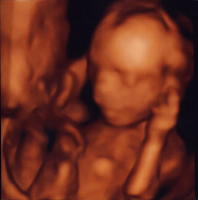

21.) És elérkezett a nagy nap: POZITÍVET TESZTELTEM, s azóta várandós kismama vagyok. :))))

24.) Riadalom, de szerencsére Zsebi Baba erősen kapaszkodik. :)

+1.) 23. hetet betöltve lépek át 2013. esztendőbe!